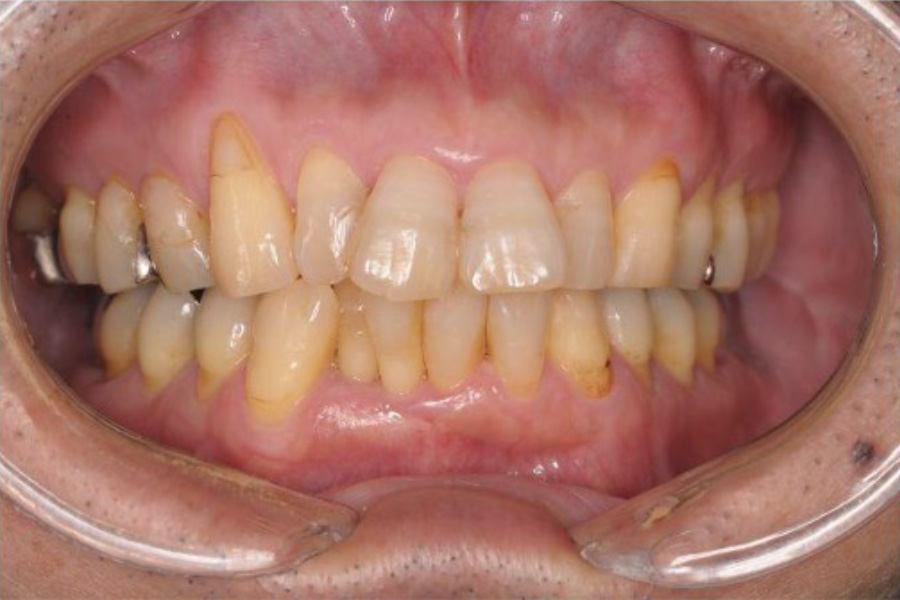

治療前

治療後

| 治療内容 | 全顎治療:歯周病治療、抜歯、根管治療、 咬合治療・矯正治療、フルメタルクラウン(保険) |